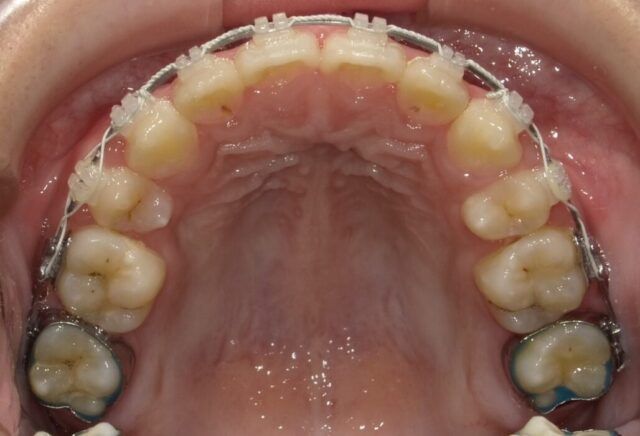

≪上顎咬合面観≫

2023年5月

2023年6月

2023年7月

2023年8月

2023年9月

2023年10月

2023年11月

2023年12月

2024年1月

2024年2月

2024年3月

2024年4月

2024年5月

2024年6月

2024年7月

2024年8月

2024年9月

2024年10月

2024年12月

2025年1月